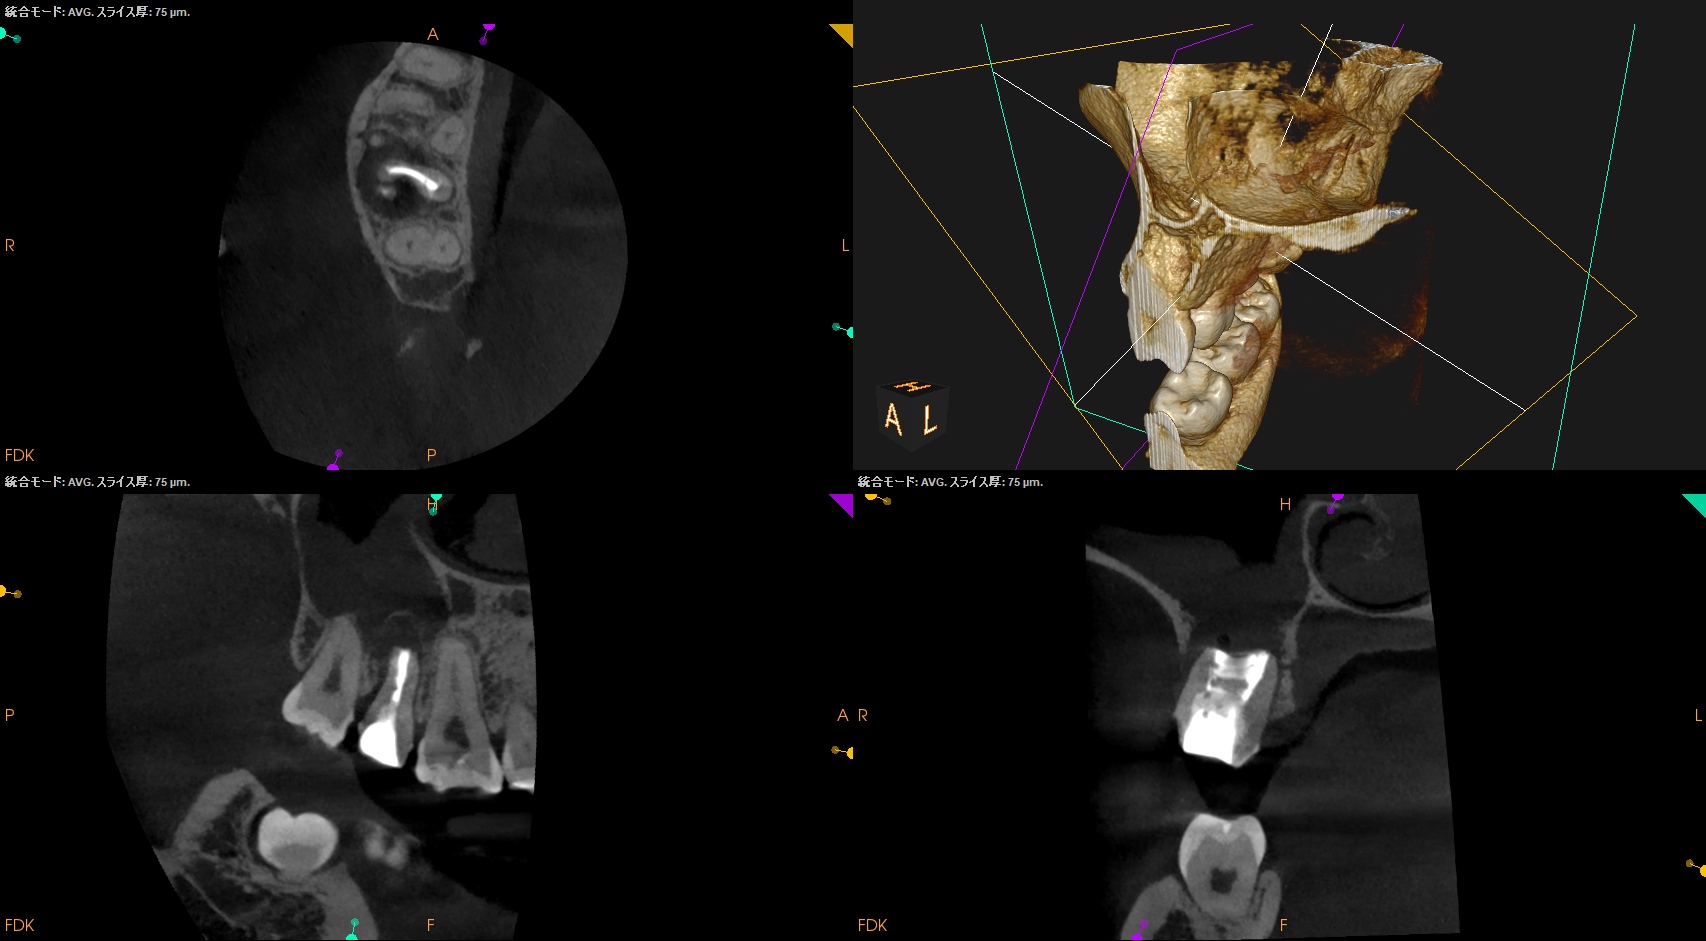

CBCT(2025.11.11)

MB

DB

P

根管は石灰化&すでに拡大済みであるので、再根管治療ではなく外科治療、つまり、Intentional Replantationの適応症である。